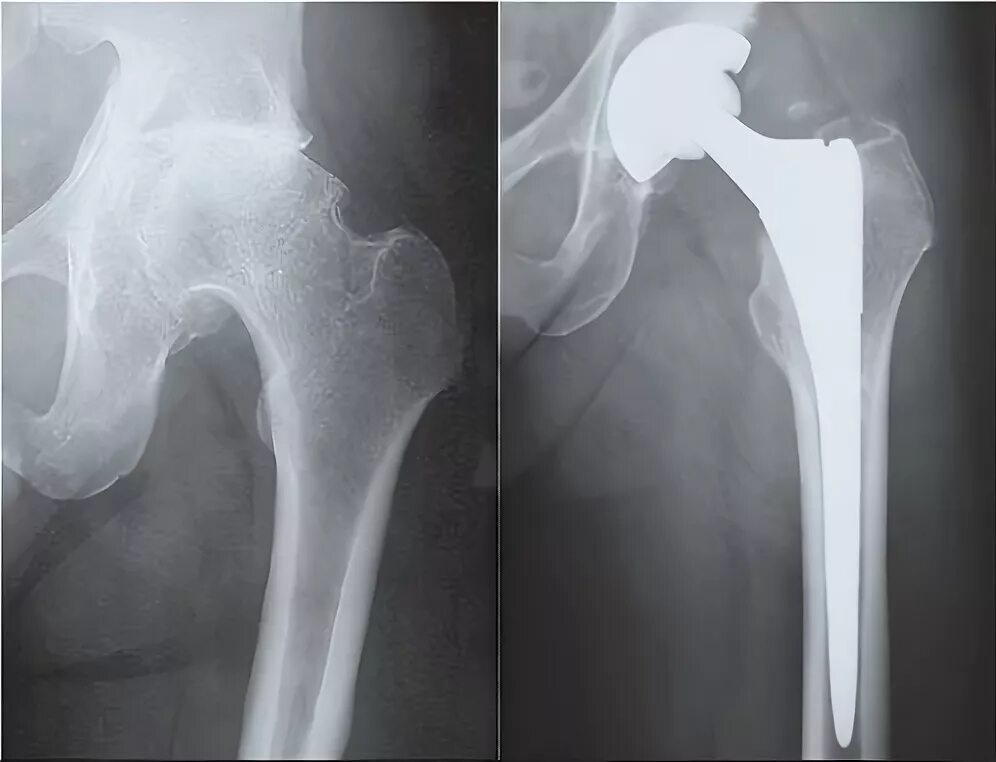

Инвалидность после эндопротезирования